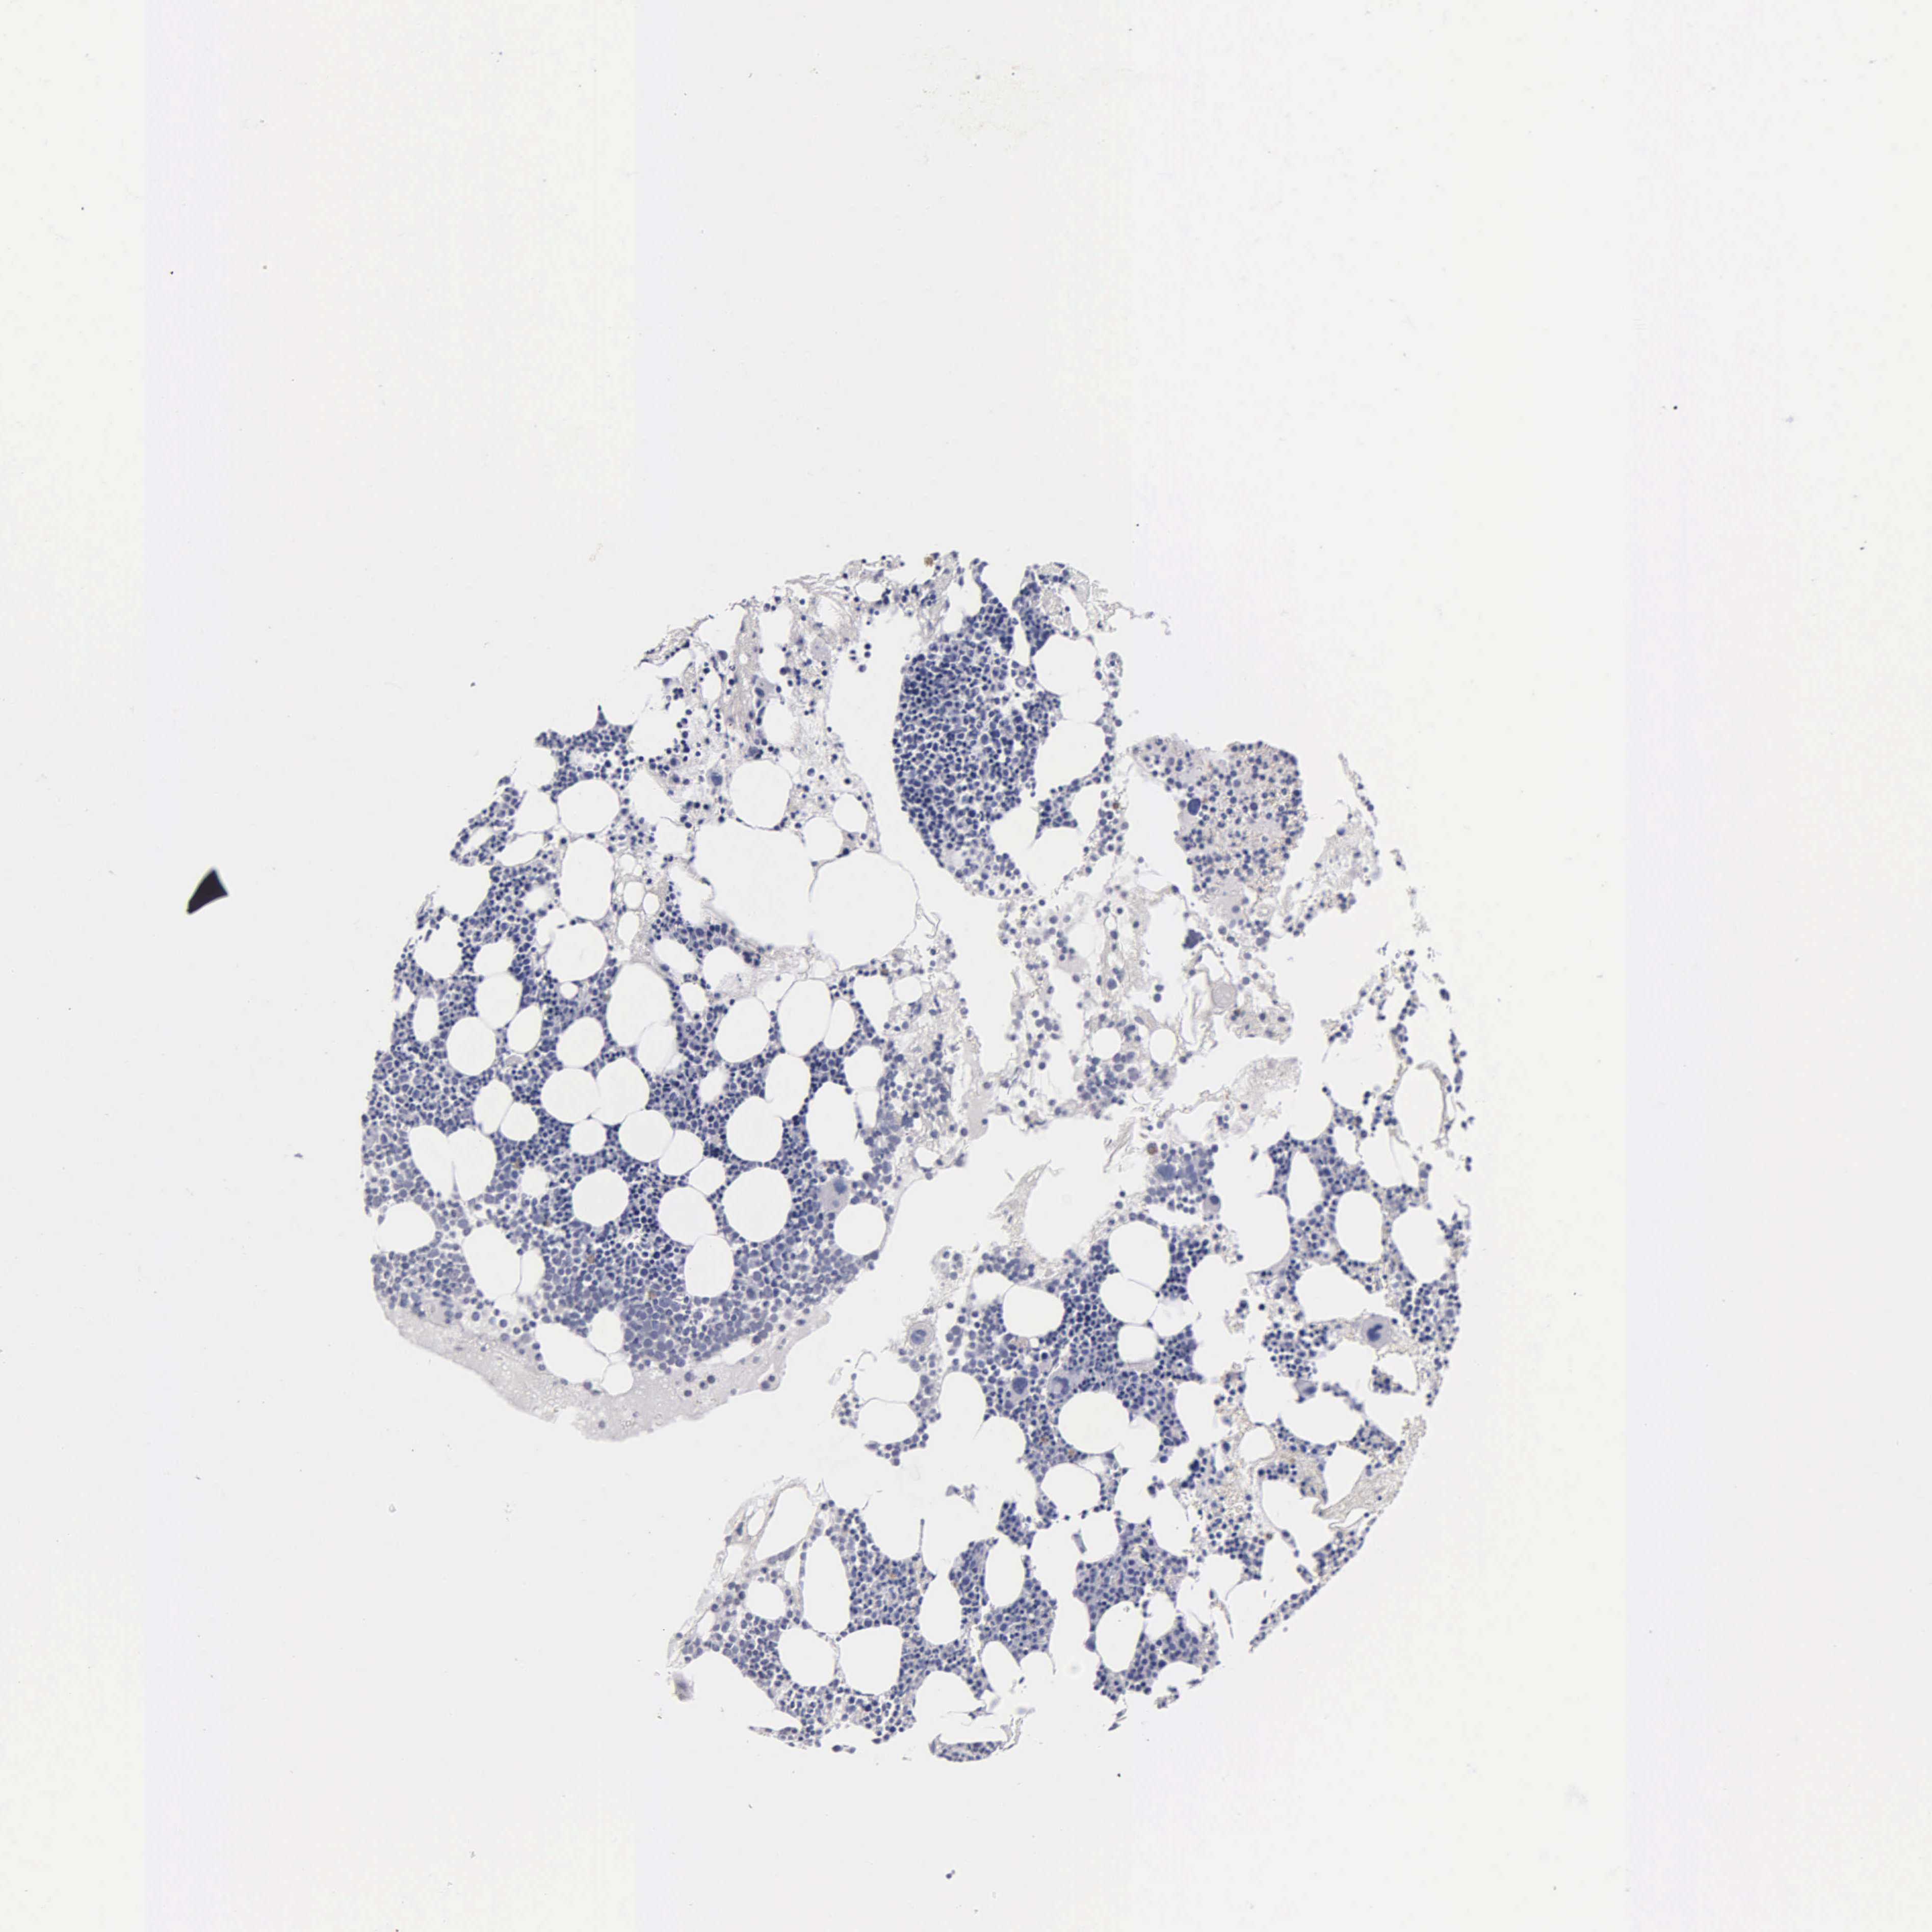

TISSUE PRIMARY DATA BONE MARROW Show tissue menu

BONE MARROW - Antibody stainingi

Antibody staining in the annotated cell types in the current human tissue is reported as not detected, low, medium, or high, based on conventional immunohistochemistry profiling in selected tissues. This score is based on the combination of the staining intensity and fraction of stained cells.

Each image is clickable and will lead to virtual microscopy that enables deeper exploration of all samples and also displays staining intensity scores, fraction scores and subcellular localization as well as patient and tissue information for each sample.

Information about each individual sample is listed below, including gender, age, a tissue section image and estimated fractions of cell types. nTPM (normalized transcripts per million) values give a quantification of the gene abundance which is comparable between different genes and samples.

Female, age N/A

Bone marrow sample 97

nTPM: 198.2

Cell types%

Myelopoietic cells:

50

Erythropoietic cells:

30

Lymphocytes:

10

Monocytes:

5

Blastic cells: